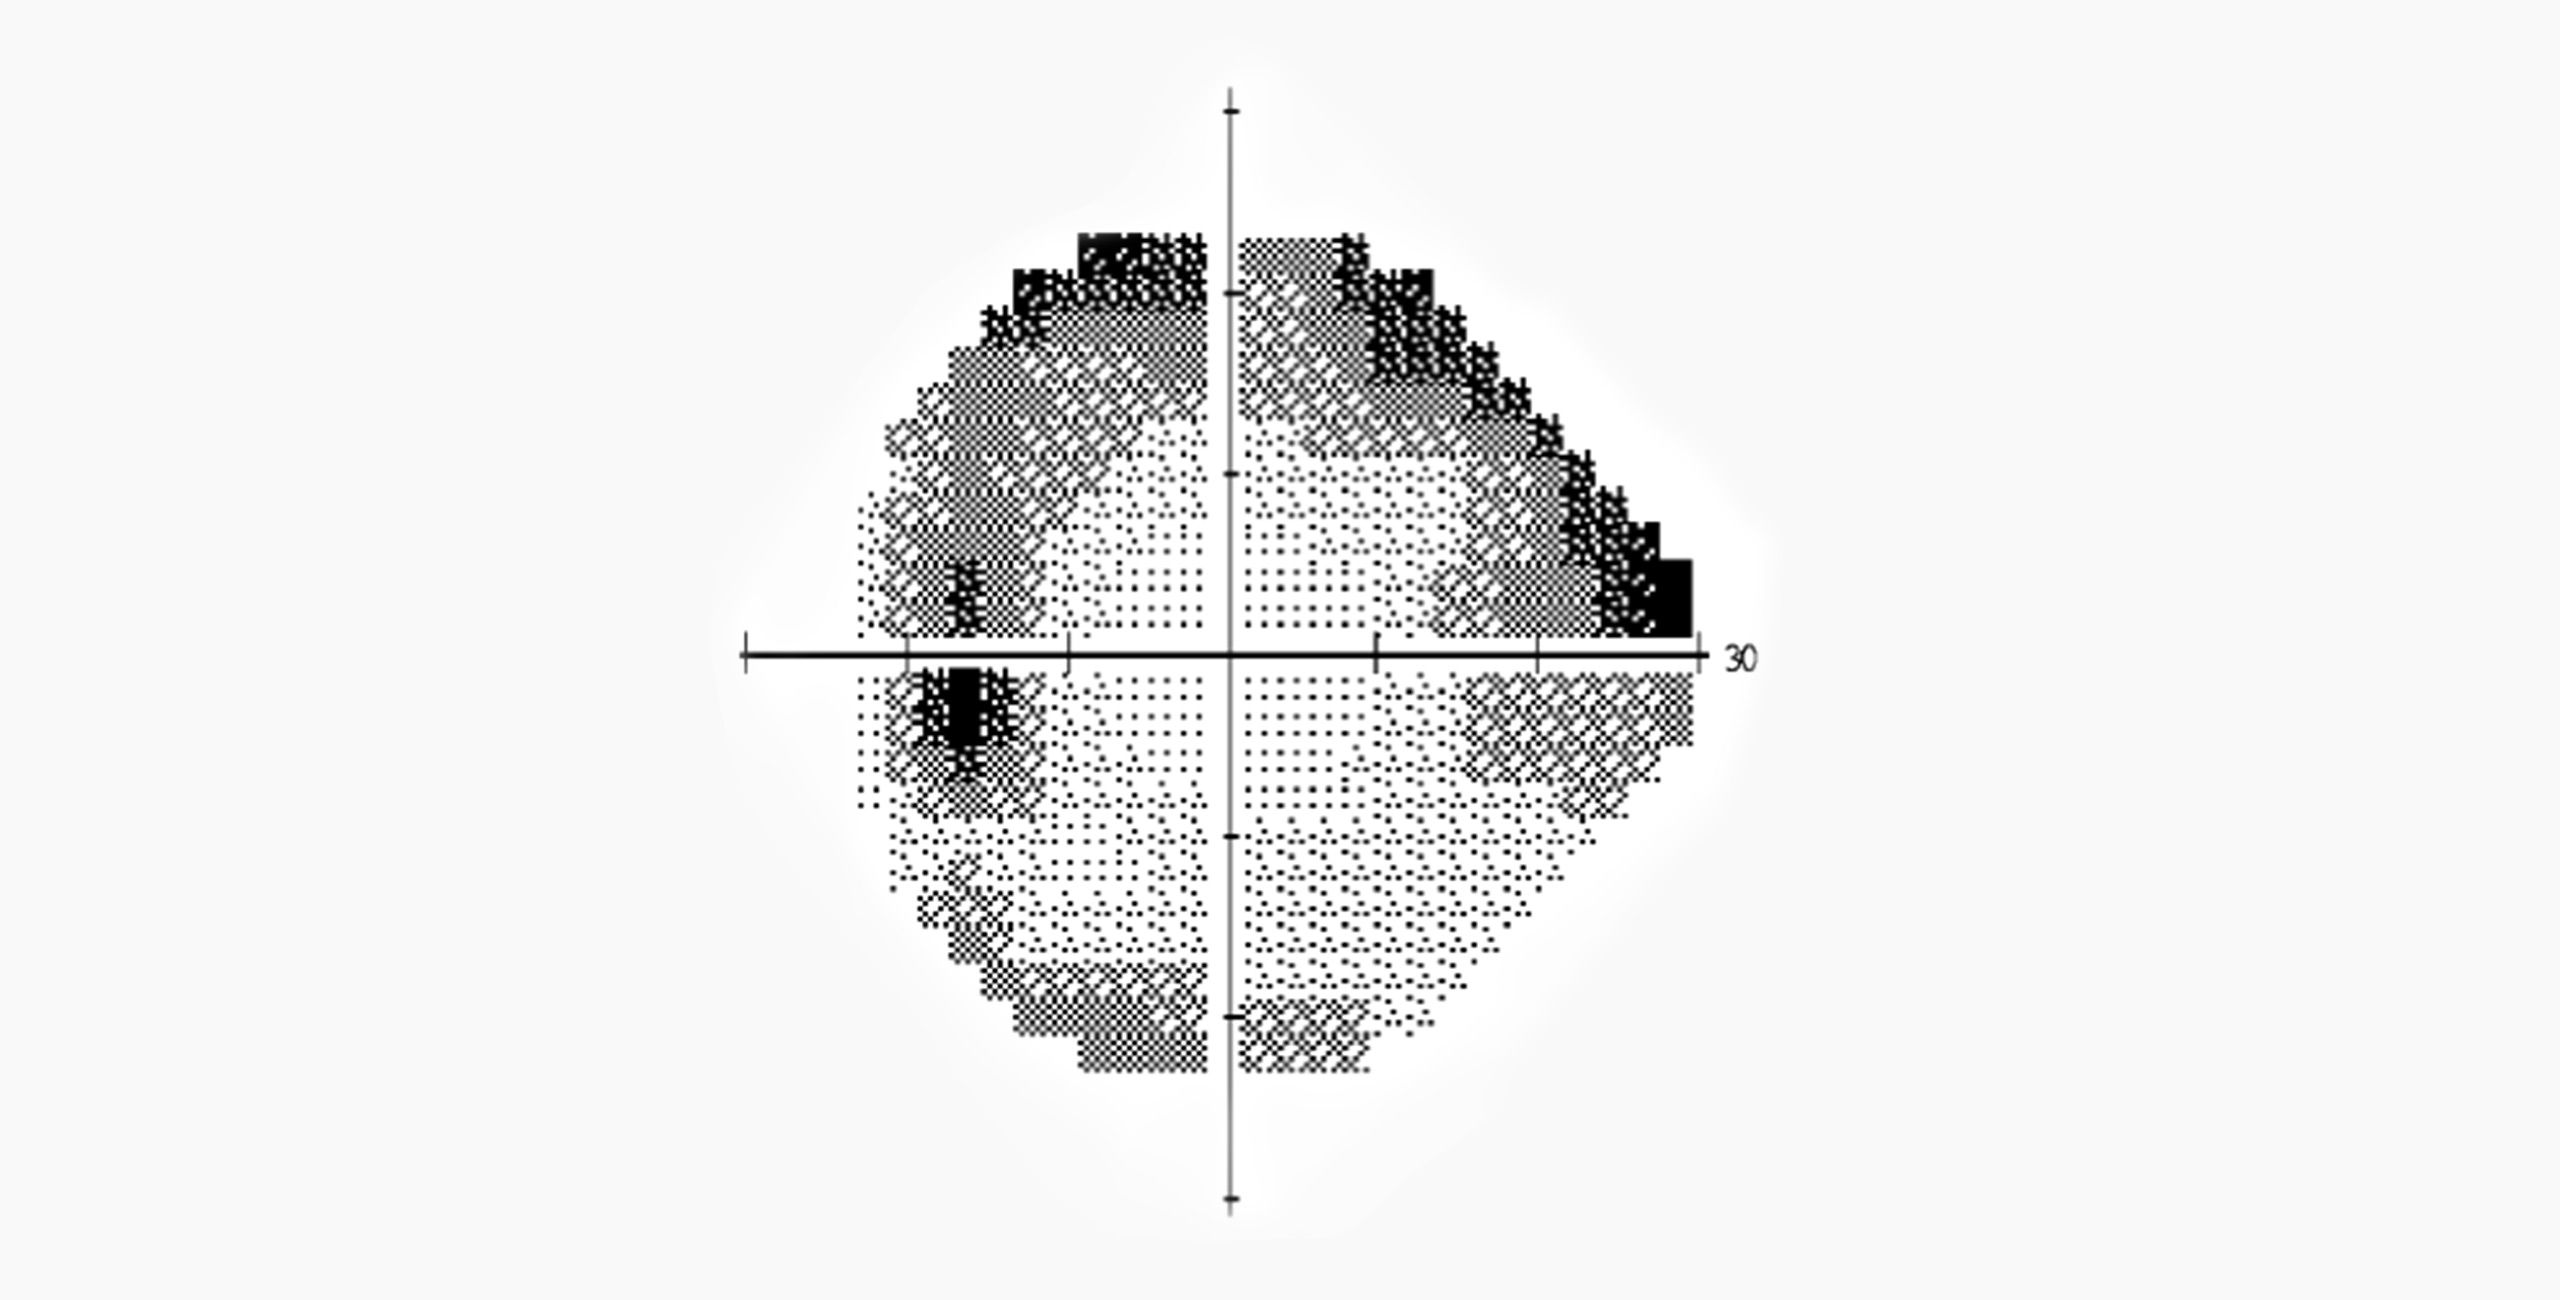

Au début, le glaucome peut être asymptomatique et progresser lentement sans causer de symptômes perceptibles. Cependant, à mesure que la maladie progresse, les patients peuvent éprouver une vision floue ou trouble, des halos autour des lumières, une diminution de la vision périphérique. En l’absence de traitement, le glaucome peut entraîner une perte de vision irréversible et même la cécité.

Le diagnostic du glaucome implique généralement un examen ophtalmologique complet, comprenant une mesure de la pression intraoculaire, une évaluation du champ visuel, une analyse du nerf optique et de la tête du nerf optique, ainsi qu’une évaluation de la chambre antérieure de l’œil à la biomicroscopie en lampe à fente. Des tests spécialisés tels que la tomographie par cohérence optique (OCT) peuvent également être utilisés pour évaluer la structure du nerf optique.